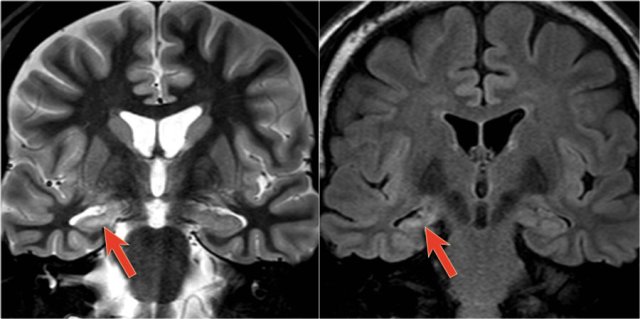

T2WI and T2* gradient echo show multiple cavernomas.

Notice the popcorn appearance with peripheral rim of hemosiderin on the T2WI.

The lesions are almost completely black on the gradient echo due to blooming artefacts.

T2* and susceptibility weighted imaging (SWI) markedly increase the sensitivity of MRI to detect small cavernomas.

The five black dots in the left cerebral hemisphere on the T2* are also cavernomas and are not visible on the T2WI.